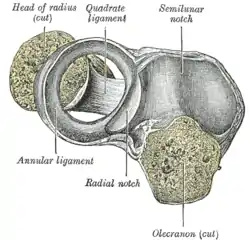

Annular ligament of radius, from above. The head of the radius has been sawn off and the bone dislodged from the ligament. | |

The annular ligament is attached by both its ends to the anterior and posterior margins of the radial notch of the ulna, together with which it forms the articular surface that surrounds the head and neck of the radius. The ligament is strong and well defined, yet its flexibility permits the slightly oval head of the radius to rotate freely during pronation and supination.[4][5]

The head of the radius is wider than the bone's neck, and, because the annular ligament embraces both, the radial head is "trapped" inside the ligament which thus acts to prevent distal displacement of the radius.[4] It helps to stabilise the proximal radial head,[6] and the radioulnar joint.[7]

A thickened band which extends from the inferior border of the annular ligament below the radial notch to the neck of the radius is known as the quadrate ligament.[1]